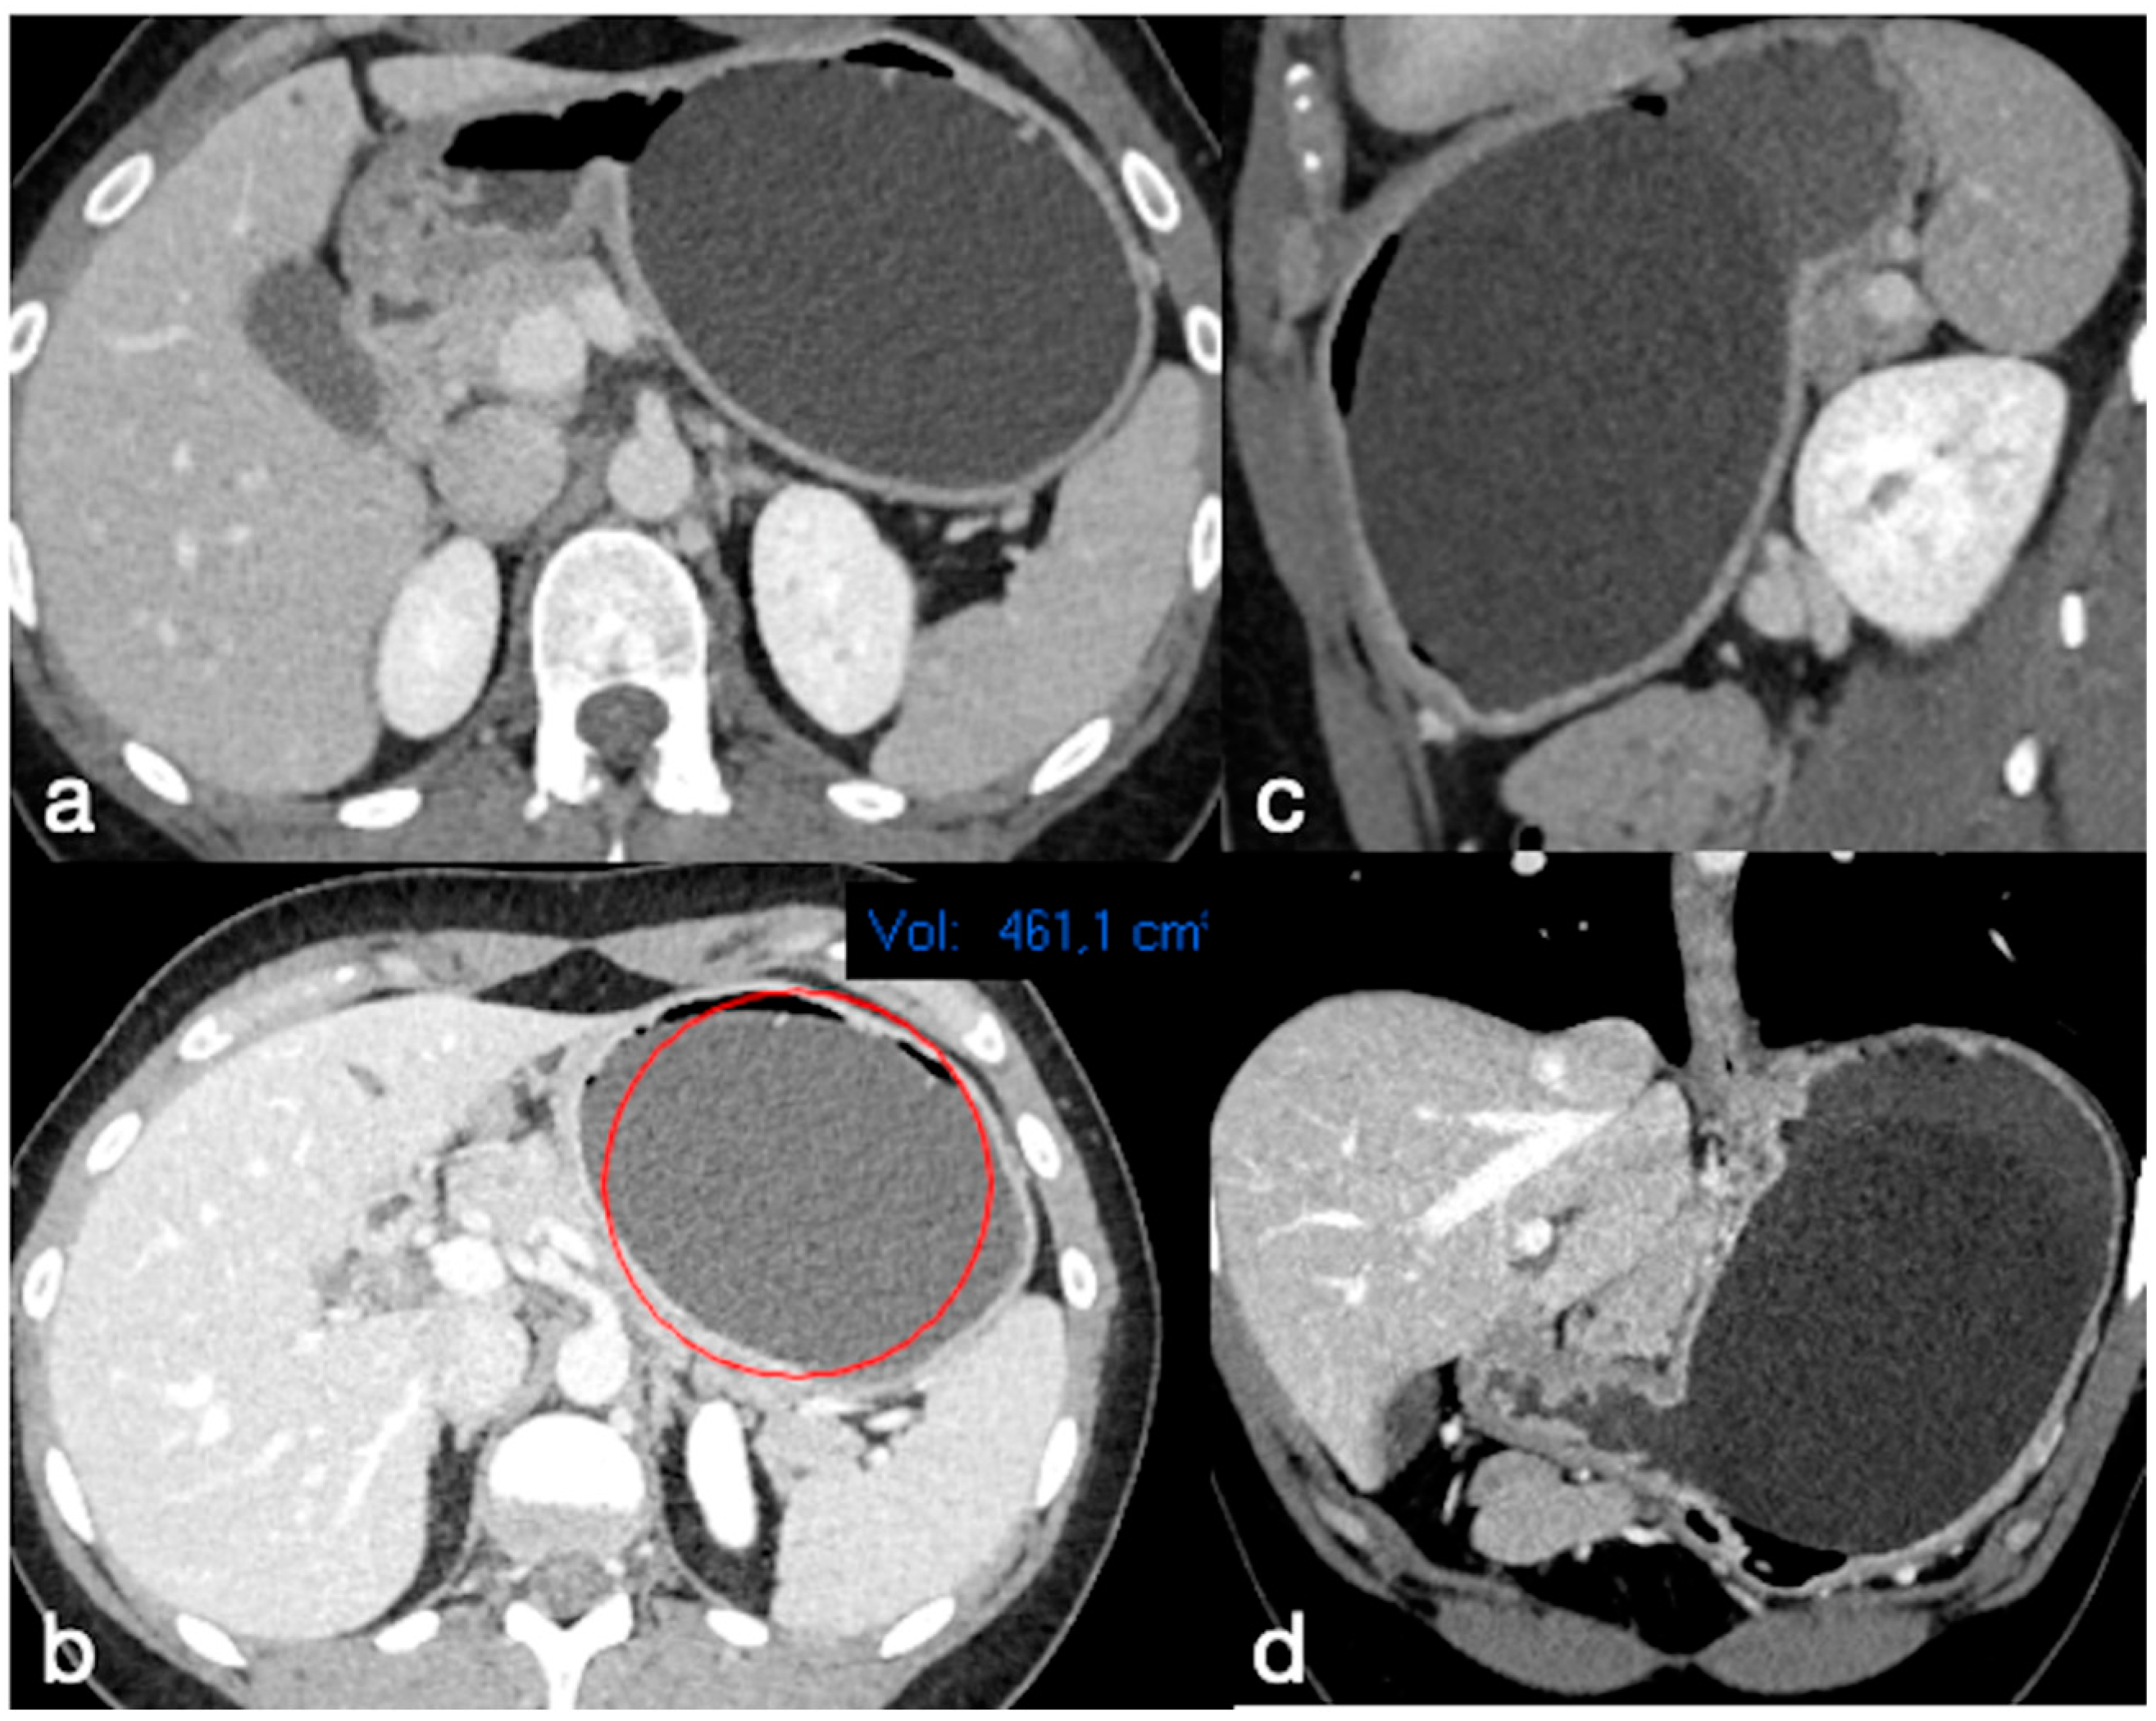

From www.mdpi.com

Diagnostics Free FullText Common, Less Common, and Unexpected Pain In Chest When Swallowing After Gastric Sleeve  Nausea can occur after a. Find out the causes, symptoms, and tips for abdominal,.   in patients with dysphagia after sleeve gastrectomy and evidence for narrowing of the gastric sleeve,. You may have incisional soreness and/or gas discomfort.   learn how long it takes to recover from gastric sleeve surgery, what to expect during the first weeks, and how to. Pain In Chest When Swallowing After Gastric Sleeve.